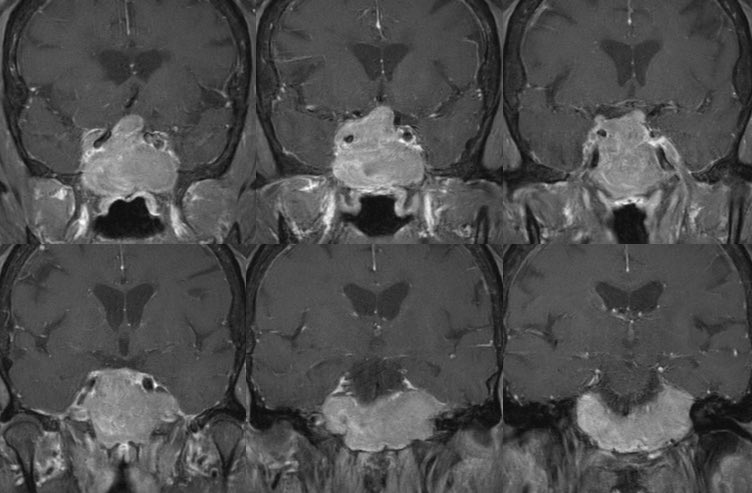

I mentored future radiologist Dr Niharika Praveen to publish this case on @radiopaedia ❓ Can you work out what background disease this person has? ❓ Which complications have arisen? Full answer over weekend with link to case (w/ stacks & annotations)